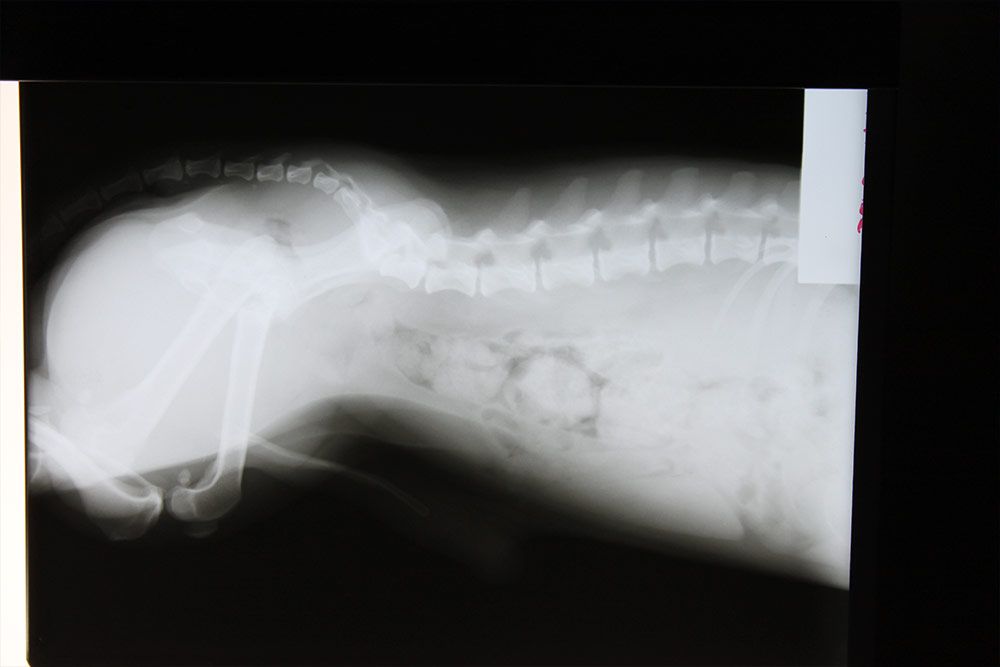

La rapidez y la precisión resultan fundamentales a la hora de detectar y tratar diferentes patologías que afectan a las mascotas y gracias a nuestro servicio de diagnóstico veterinario por imagen en Pinto podemos conseguir ambas. Gracias al uso de diferentes técnicas de imagen directa conseguimos emitir pronósticos fiables y prescribir los tratamientos y/o actuaciones que hay que llevar a cabo para alcanzar la mejor solución en cada caso.

En Clínica Veterinaria La Tenería no escatimamos en recursos, con el objetivo de poner a disposición de tus mascotas los mejores medios. Por eso, en nuestro centro contamos con los más modernos sistemas de diagnóstico veterinario por imagen en Pinto; concretamente, con equipos para realizar radiografías, ecografías y electrocardiogramas.

El recurso al diagnóstico veterinario por imagen en Pinto resulta de gran utilidad para valorar patologías de los órganos internos, como el corazón, el hígado o los riñones. También nos aporta información sobre el estado de los tejidos blandos, los huesos o las articulaciones. Al ofrecer imágenes en tiempo real, nos permite actuar con mayor celeridad en caso de detectar algún problema en la mascota.